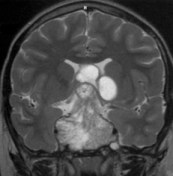

l’imagerie

il s’agit d’un tumeur supra-sellaire souvent calcifiée et kystique

l’imagerie étudie ses rapports avec l’hypothalamus, les voies visuelles, les structures du sinus caverneux.